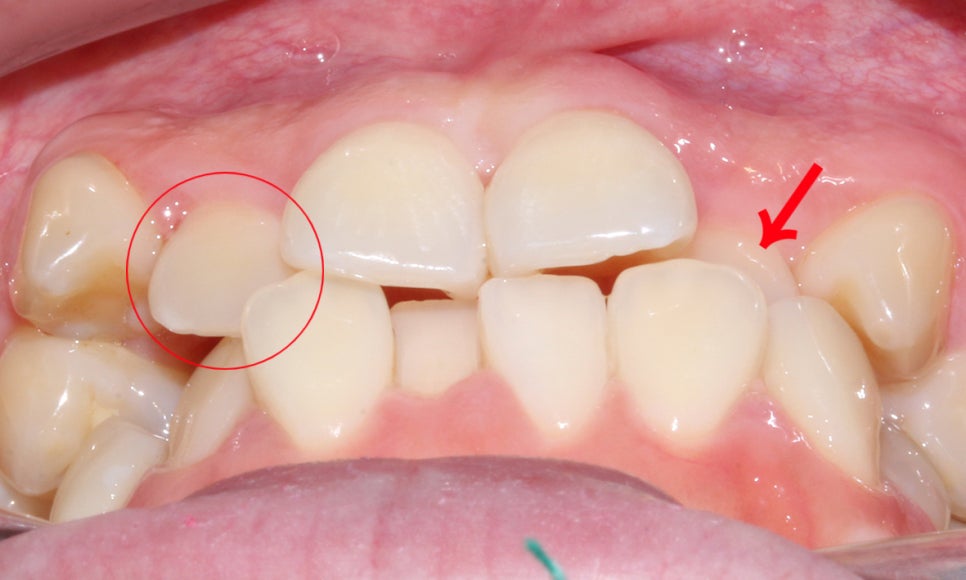

위처럼 송곳니덧니가 제대로 맹출될 자리가 부족하여

측절치를 중절치 뒤로 밀어낸 모습입니다.

전치부의 측면 사진을 보시면

전치부 치아의 크라우딩으로 인해

안모가 약간 돌출되어 보이는 모습으로

전치부 치열을 가지런하게 교정한다면

이러한 돌출감이 크게 개선될 것으로 예상됩니다.

송곳니덧니 증상으로 인해 상악의

측절치가 크게 삐뚤어진 모습인데요,

측절치가 이상적인 안모의 형태를

갖추지 못하고 치아 안쪽으로 뻐드러진 모습입니다.